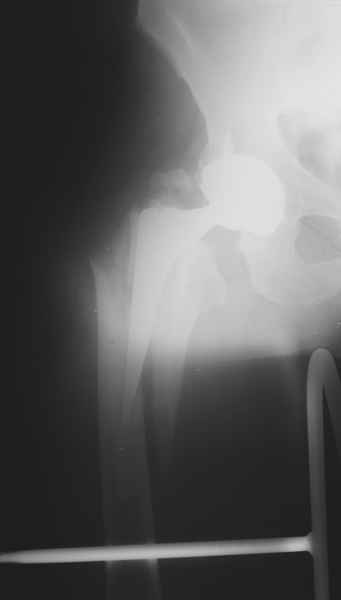

Уважаемые коллеги, продолжая дискуссию, начатую на "Вреденовских чтениях", хочу сказать, что принципиально сущестует два возможных варианта лечения.

1.Остеосинтез на ножке. Мне кажется, что применительно к этому случаю малоперспективный вариант. Синтез хорош, когда можно его выполнить в малоинвазивном исполнении и достигнуть стабильности. Действительно, если ножка б/цементной фиксации после этого не будет иметь фиксации, то ревизия не будет иметь проблем. В представленном случае стабильность синтеза сомнительная, а проведение доп.иммобилизации приведет к контрактуре суставов.

2. Применение ножки дистальной фиксации, мы отдаем предпочтение ножке Вагнера с фиксацией проксимального отдела на ножке. Более травматичное вмешательство, но при стабильной фиксации ножки реабилитация идет в обычном режиме.

Хочется показать два подобных случая, П-ка З. 72 лет и п-т Г. 80 лет. Сразу принимаю замечание, что это были ножки цементной фиксации, просто под руками не было бесцементника.